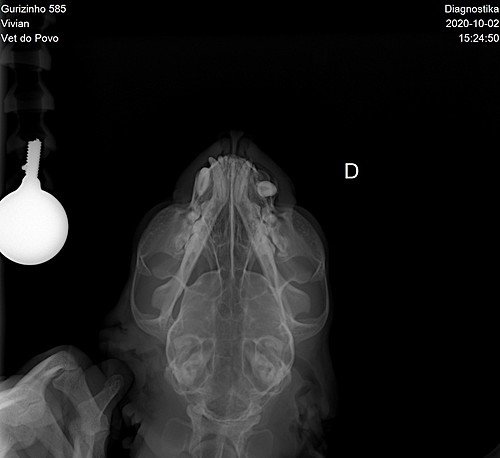

Através do raio x, a veterinária me orientou que o melhor a fazer é extrair o dente canino, o dente que quebrou e se não extrair é perigoso aparecer outras complicações, como uma inflamação forte, só quero dar o melhor a ele e estou aqui pedindo sua ajuda, pois teria que passar os gastos no cartão dos meus pais e não sei como irei pagar. Desde já muito obrigada.